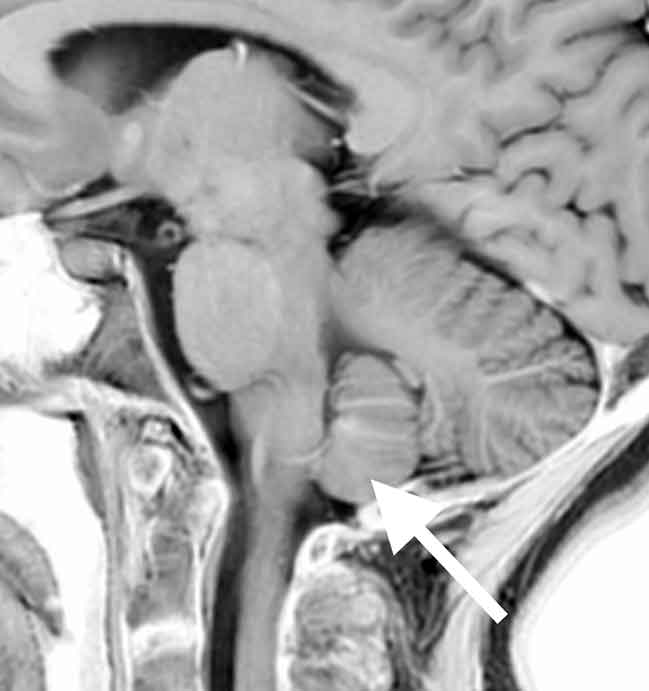

【症例報告】40代後半の女性で、約2週間前から後頭部の痛みがあり、立ち上がると痛みが強くなり、横になると治まるという特徴。片頭痛の痛み方とは違うと感じ受診。

MRI検査では、

頭痛が1週間以上続く原因

小脳扁桃という部分が若干下に下がっている所見を認めました。

立つと痛みが強くなり、横になるとなくなるという特徴とこの所見から、脳脊髄液減少症と診断。この疾患は、脳脊髄液が足りなくなるため、脳が後ろに引っ張られて後頭部の痛みを生じます。さらに、脳脊髄液が減る原因を調べるため大学病院へ紹介。